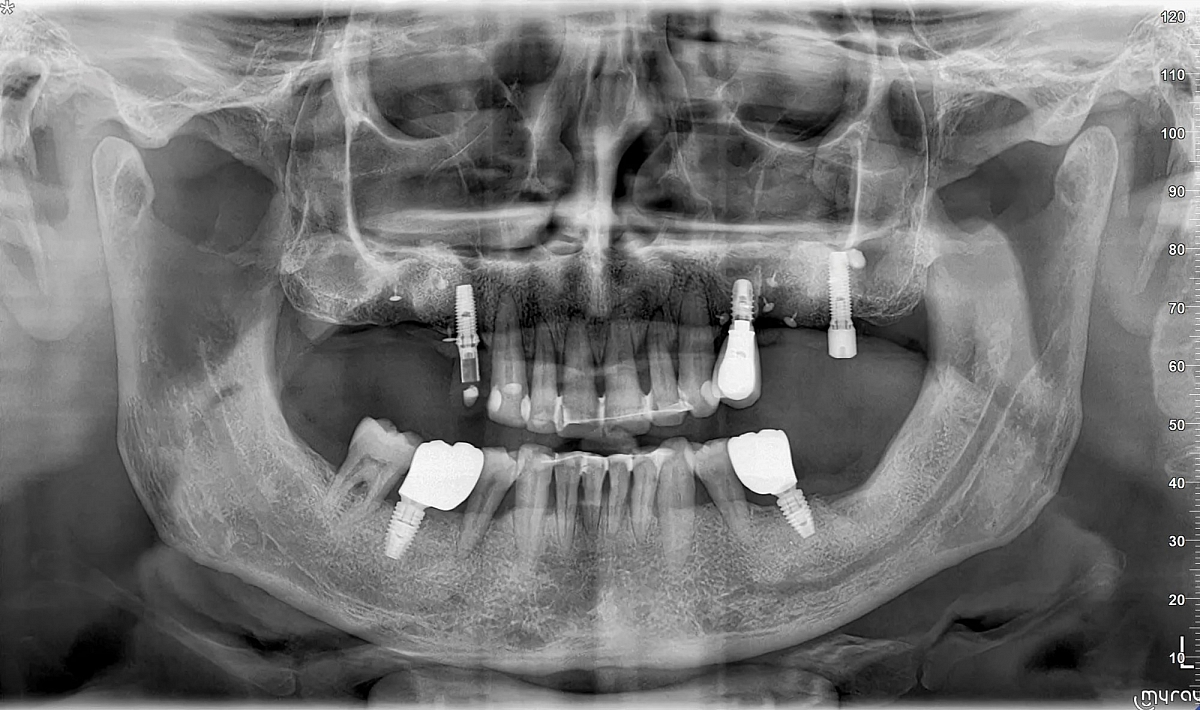

Diagnostinės galimybės

2D vaizdai

- Panoraminiai (PAN) vaizdai su keliais fokusavimo sluoksniais

- Detalios žandikaulių sričių projekcijos

3D CBCT vaizdai

- SuperHD CBCT su MultiFOV funkcija nuo mažiausio (4x4) iki didžiausio (15x16) lauko

- Greitas 360° skenavimas ir mažos dozės protokolai

- Tiksli kaulinės struktūros diagnostika implantologijai, chirurgijai, ortodontijai ir ENT analizėms